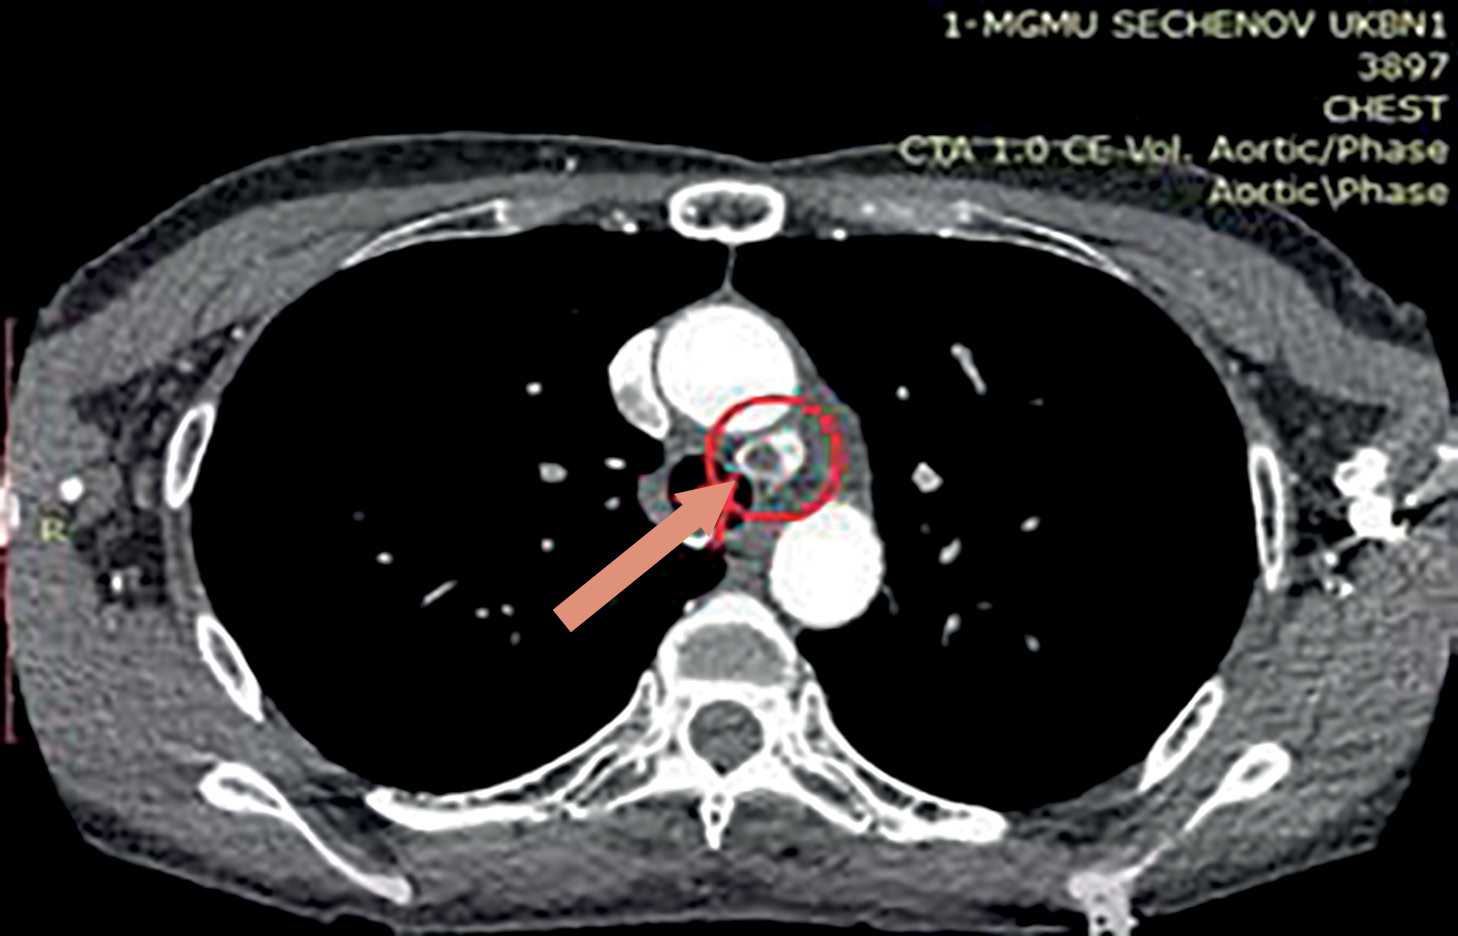

5. Рисунок 5. Томограмма, аксиальная проекция. Новообразование ОЩЖ указано стрелкой. | |